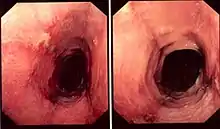

| Pathology image of lymphocytic esophagitis (H&E stain). The image demonstrates common findings in the condition: dense peripapillary lymphocytic infiltrate with spongiosis (arrow), and absence of neutrophils and eosinophils. | |

While the histologic changes in the biopsies are characterized by the presence of an inflammatory infiltrate, consisting primarily of lymphocytes in the absence of other inflammatory cells such as granulocytes, the criteria for making the diagnosis are still unclear.[1][4] The location of the biopsies, cutoff of number of lymphocytes found in each high-power field of view of the microscope, the presence of spongiosis, and the need for immunohistochemical staining to define lymphocytes are all unclear still.[1]